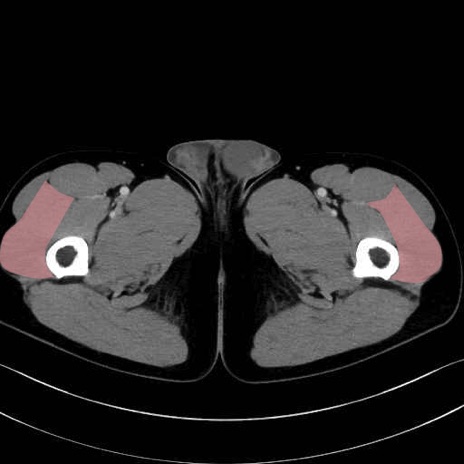

外側広筋(vastus lateralis) のCT画像の解剖

外側広筋 (Vastus lateralis)